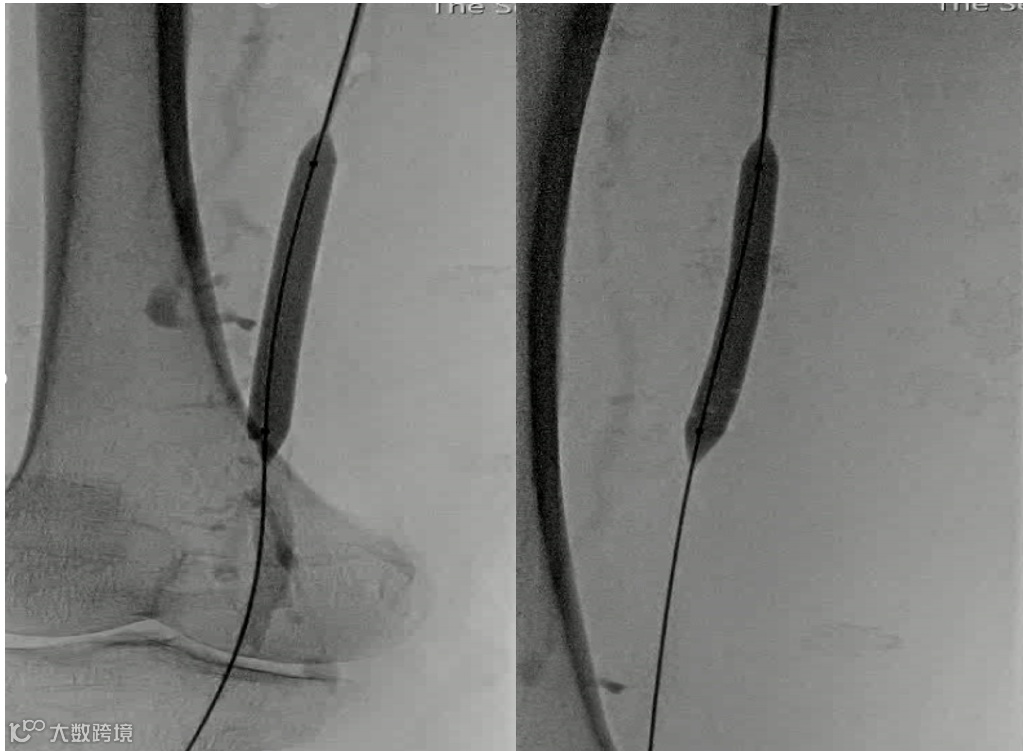

手术过程